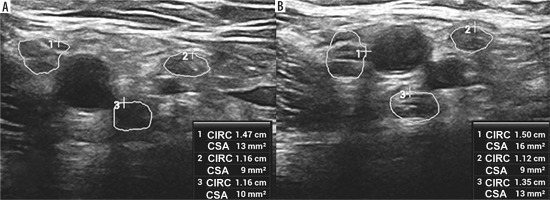

Figure 3

High-resolution ultrasound image of the C5 (A, B) and C6 (C, D) roots with cross sectional area (CSA) measurements in 57-year-old patient with Parsonage-Turner syndrome. Root swelling, reflected by increased CSA and circumference (CIRC) detected on the symptomatic side. Images obtained by author with a 5-20 MHz linear probe of the Mindray Resona I9